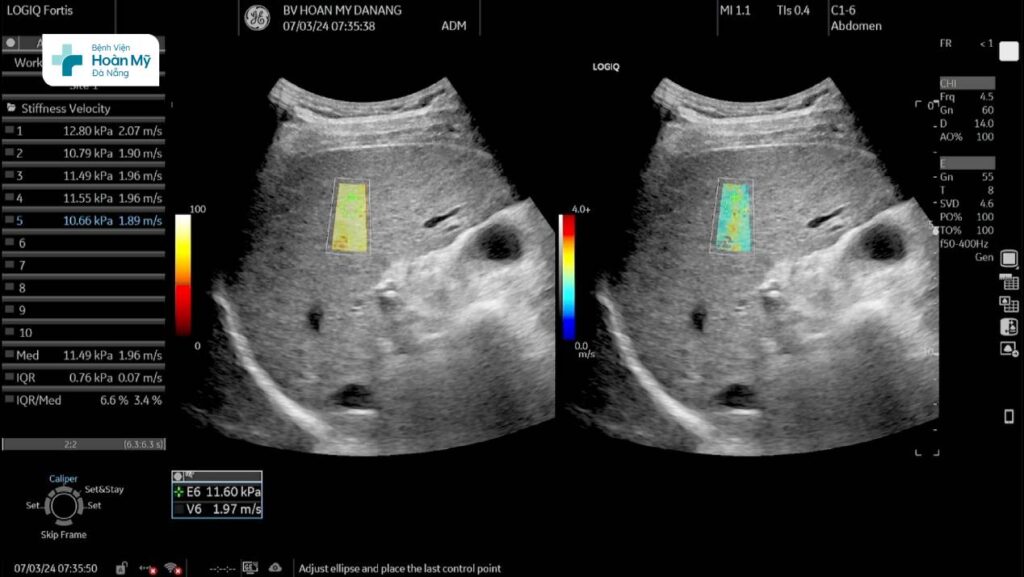

Siêu âm chẩn đoán mức độ xơ hóa gan trên máy siêu âm cao cấp LOGIQ Fortis thế hệ mới

Một ví dụ về ứng dụng của siêu âm đàn hồi mô như sau: Một người bệnh nam, gần đây thấy mệt mỏi nên đến khám tại Bệnh viện Hoàn Mỹ Đà Nẵng, được bác sĩ cho siêu âm bụng, trên siêu âm thường quy thấy cấu trúc gan thô, khi thực hiện siêu âm đàn hồi mô gan đo được độ cứng 11,49 kPa (IQR/Med # 6,6%) tương ứng xơ hóa gan độ 3.